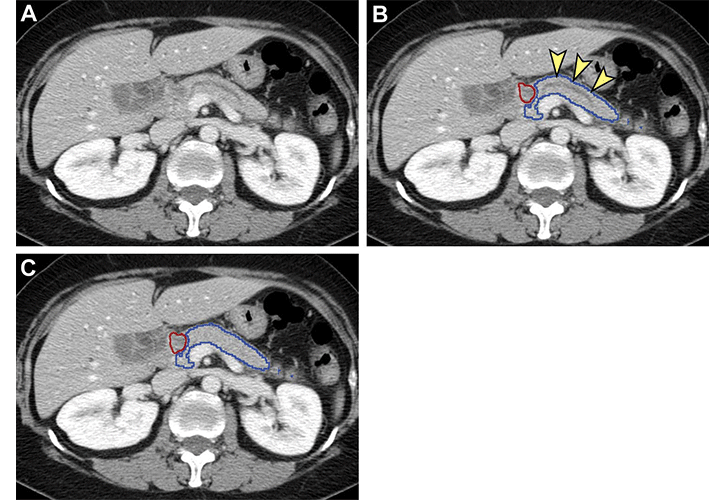

Analysis of nontumorous portion of pancreas with or without secondary signs of pancreatic cancer by classification models. Blue outline represents the portion of the pancreas analyzed with classification models. The tumor (red outline) was not identified by the segmentation model; thus, it was not analyzed by classification models. (A) Unannotated CT image in a patient with pancreatic head cancer. (B) Nontumorous portion of the pancreas shows secondary signs of pancreatic cancer (dilation of pancreatic duct with abrupt cutoff [arrowheads]) and was classified as cancerous by the classification models. (C) Nontumorous portion of the pancreas appeared normal and was classified as noncancerous after the dilated duct was replaced and imputed with surrounding normal-appearing pancreas parenchyma.